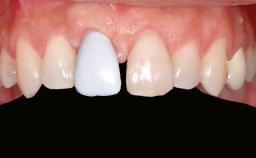

Prosthesis Type FDP